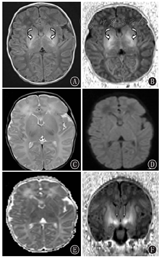

脑水肿消失且新生儿出生2~4周行常规MRI可有效评估其远期结局,在符合HIE标准的婴儿中,最常见的病变是BGT(图5)[5]。BGT的病变常伴皮质和皮质下白质损伤,最典型的是在中央沟周围和内侧颞叶,BGT病变的严重程度决定了脑瘫的严重程度和性质。

图5

T1WI及DWI:缺氧缺血性脑病患儿双侧基底核及丘脑高信号(箭头所示)

Figure 5

T1WI and DWI:bilateral basal nuclei and thalamus hyperintensity in children with hypoxic-ischemic encephalopathy (arrow showed)